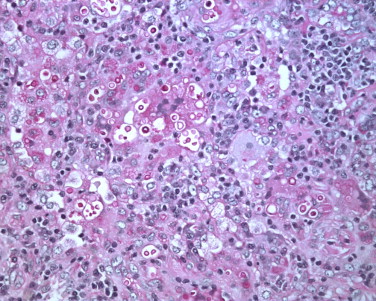

Por ejemplo, en la técnica PAS, que se utiliza para detectar azúcares reductores en muestras histológicas o citológicas, el reactivo de Schiff reacciona con los grupos aldehído de estos azúcares. Esto da como resultado la aparición de un color rojo característico en las áreas que contienen azúcares reductores. La intensidad del color rojo está relacionada con la cantidad de azúcares reductores presentes en la muestra.

- Identificación de glucógeno: La técnica PAS se utiliza comúnmente para demostrar la presencia de glucógeno en las células, especialmente en tejidos como el hígado y el músculo, donde se almacena como fuente de energía. La coloración rosa-magenta característica permite identificar claramente las áreas que contienen glucógeno.